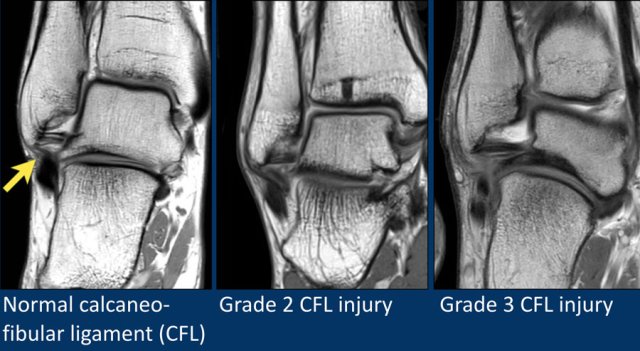

CFL

The Calcaneofibular ligament runs from the distal fibula to the lateral side of the calcaneus and is best appreciated on coronal images.

The CFL passes two joints, the talocrural joint and the talocalcaneal joint.

Isolated injury of the CFL is uncommon.

Most of the time the ATFL is injured as well.